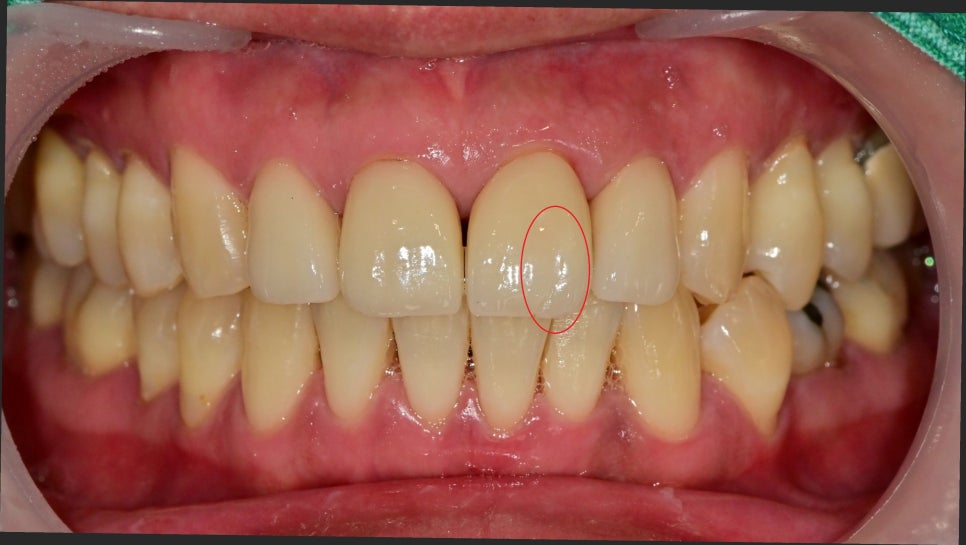

사실 처음 봤을 때 과거에 만드셨지만 너무 자연스럽게 잘하셔서 보철물이 아닌 자연치아인 줄 알았지만

사진에서와 같이 갈라지고 조각이 움직이고 있는 상태였습니다.

안쪽에서 보면 명확하게 보입니다.

앞니 4개를 하셨는데 그중에 2개가 금이 생겨있었습니다.